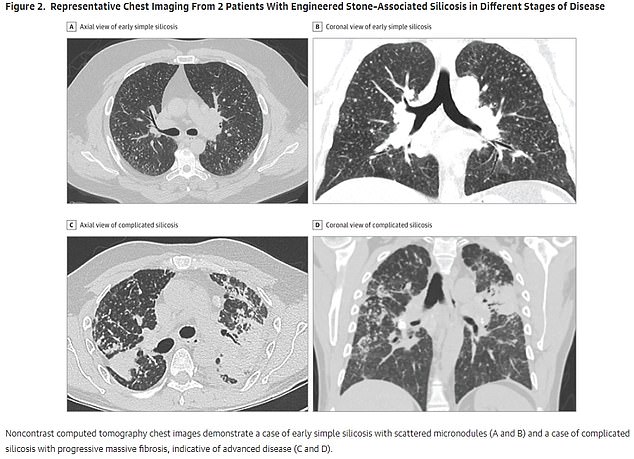

Once inhaled, silica particles lodge deep in the lungs, provoking inflammation and permanent scarring that gradually impair breathing.[1] People with silicosis may develop progressive shortness of breath, persistent cough, fatigue, and chest pain, and severe cases can lead to respiratory failure, increased susceptibility to infections, chronic obstructive pulmonary disease, autoimmune disorders, and lung cancer.[1] Because the damage is irreversible and there is no cure, prevention of exposure is the only reliable way to avoid this disease.[1][4]